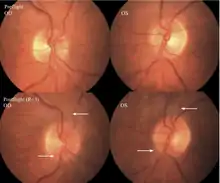

The first U.S. case of visual changes observed on orbit was reported by a long-duration astronaut that noticed a marked decrease in near-visual acuity throughout his mission on board the ISS, but at no time reported headaches, transient visual obscurations, pulsatile tinnitus or diplopia (double vision). His postflight fundus examination (Figure 1) revealed choroidal folds below the optic disc and a single cotton-wool spot in the inferior arcade of the right eye. The acquired choroidal folds gradually improved, but were still present 3 year postflight. The left eye examination was normal. There was no documented evidence of optic-disc edema in either eye. Brain MRI, lumbar puncture, and OCT were not performed preflight or postflight on this astronaut.[3]

The seventh case of visual changes associated with spaceflight is significant in that it was eventually treated postflight. Approximately 2 months into the ISS mission, the astronaut reported a progressive decrease in his near and far acuity in both eyes. The ISS cabin pressure, CO2 and O2 levels were reported to be within normal operating limits and the astronaut was not exposed to any toxic substances. He never experienced losses in subjective best-corrected acuity, color vision or stereopsis. A fundus examination revealed a grade 1 bilateral optic-disc edema and choroidal folds (Figure 15).[3]